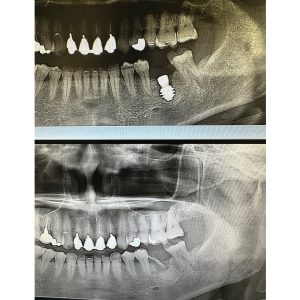

朝から埋伏抜歯にインプラント埋入

ワンドリルで楽

スーパーワイド径7.5 L7ミリは難しい

長さより表面積が重要です!

出し入れ3回 汗